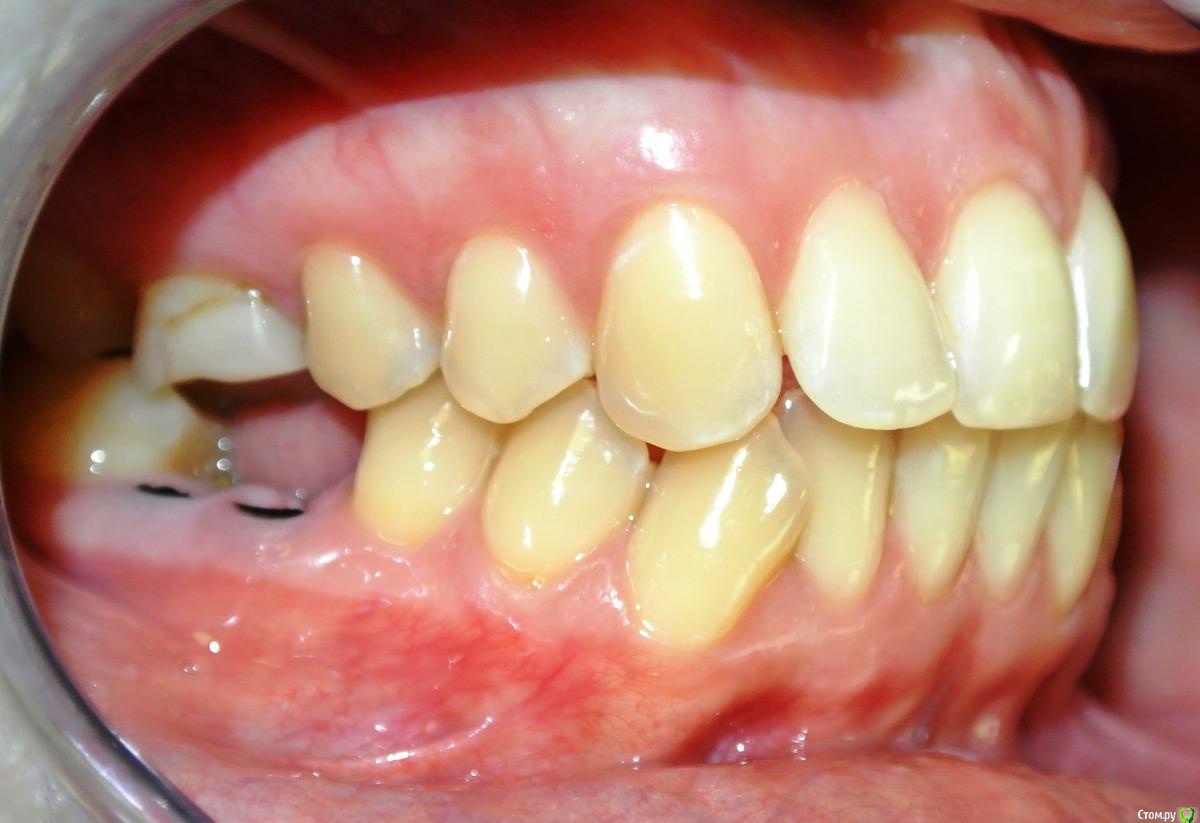

Dina_N Опубликовано 2 апреля, 2015 Поделиться Опубликовано 2 апреля, 2015 Пациентка Н., 30 лет. Жалоба на смещение средней линии верхнего зубного ряда. Из анамнеза: зуб 1.3. удален в возрасте 9 лет (ох уж эти удаляльщики). Как можно скорректировать положение средней линии? Ссылка на комментарий

Yana guapa Опубликовано 2 апреля, 2015 Поделиться Опубликовано 2 апреля, 2015 Хорошо бы фото с улыбкой в полный фас , т.к. средние линии лица, носа, губ, ВЧ и НЧ все между собой могут не совпадать. Судя по данным фото, смещение средней линии ВЧ присутствует, но в большей степени здесь играет роль уплощение ВЧ справа. Поэтому и расширять в данном месте нужно, устранять асимметрию ВЧ, с восстановлением дефекта з/р (имплантацией клыка) . Вся ВЧ сужена. Раскрывать под клык надо. Ссылка на комментарий

229KAMA Опубликовано 11 апреля, 2015 Поделиться Опубликовано 11 апреля, 2015 Пациентка Н., 30 лет. Жалоба на смещение средней линии верхнего зубного ряда. Из анамнеза: зуб 1.3. удален в возрасте 9 лет (ох уж эти удаляльщики). Как можно скорректировать положение средней линии?DSC_7521.JPGDSC_7522.JPGDSC_7524.JPGDSC_7525.JPGDSC_7526обр.jpgDSC_7527 обр.jpgСкажите пожалуста Я вот прочитал "1.3. удален в возрасте 9 лет" -это постоянный клык вроде так по номеру и квадранту (постоянный). А на фото Я вижу его на предоставленных фотографиях , что он стоит в челюсти. Или Я вижу , что то не так. Если ошибаюсь то возможно по не опытности ? приношу свои извинения. Ссылка на комментарий